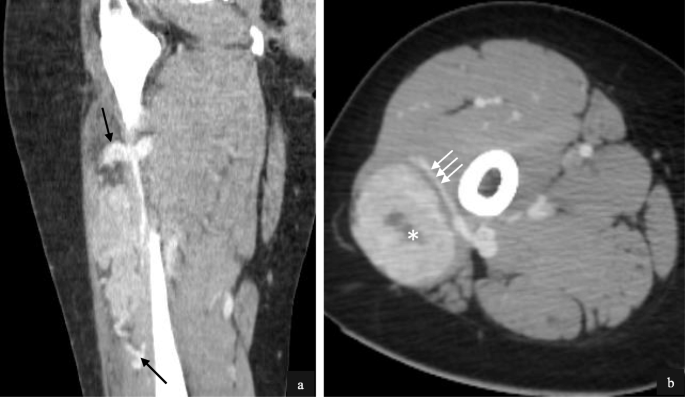

Imaging of the primary tumour on CT was available for 7/32 (22%) patients. Primary sites included the trunk (2/7), retroperitoneum/pelvis (1/7) and extremities (4/7). Mean tumour size was 6.4 cm (range 1.7–14.0 cm). All primary tumours demonstrated increased vascularity with tortuous feeding vessels (Figs. 1, 2). Necrosis was present in 5/7 cases (Fig. 2). Well-defined tumour margins were demonstrated in 4/7 primary tumours. Calcification in the primary mass was demonstrated in 1/7 cases. Haemorrhage was not of a feature of any of the primary masses imaged.

Intramuscular lower limb primary ASPS in a 16 year old female patient. Post contrast coronal (a) and axial (b) CT images demonstrate hypervascularity of the primary tumour. Feeding vessels at the upper and lower poles (a, black arrows) as well as circumferential vessels (b, white arrows) are present. Small volume necrosis is seen centrally (b, white asterisk)

Primary ASPS within the pelvis in a pelvic 22 year old female (a) and intra-abdominal primary ASPS in a 24 year old male (b) patient. Post contrast axial (a) and coronal (b) CT demonstrates large tortuous feeding vessels at the periphery of both tumours (black arrows) with marked tumour hypervascularity. Although there is significant mass effect, both masses demonstrate well defined borders with no evidence of local invasion